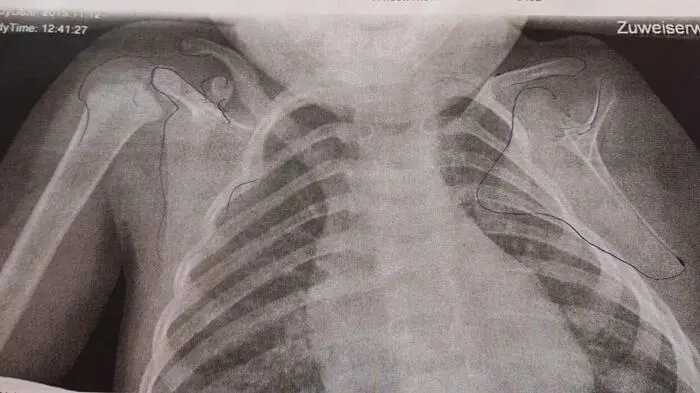

Auf dem Röntgenbild des Kindes ist die Fehlbildung an der linken Seite deutlich zu sehen

Das Kind wurde ohne Unterarm geboren